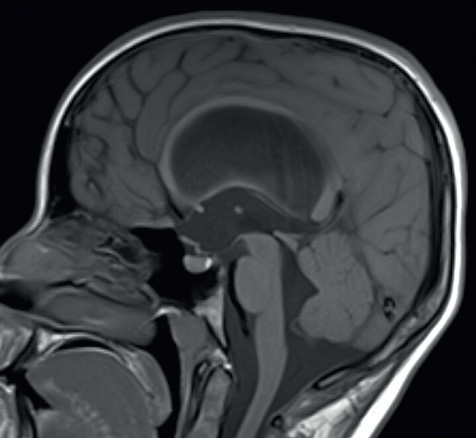

V naší kazuistice hraje ústřední roli patnáctiletá dívka, která byla sledována dětskou neuroložkou pro měsíce trvající silné bolesti hlavy. Tyto byly lokalizovány do oboustranných spánkových oblastí bez návaznosti na specifické činnosti, polohu či jiné faktory. Bolesti byly přítomny denně, dívka často vynechávala ve škole, kde se i beztak její prospěch horšil kvůli poruše pozornosti a paměti. Ošetřující neuroložka indikovala magnetickou rezonanci (MR) mozku, kde byla nalezena dilatace komorového systému (obr. 1). S tímto byla pacientka přijata do naší péče. V anamnéze nebyly vystopovány žádné rizikové faktory pro vznik hydrocefalu – perinatální anamnéza byla negativní, pacientka neprodělala žádný neuroinfekt či úraz hlavy. Na MR mozku byla viditelná výrazná dilatace komorového systému, zejména supratentoriálně, nicméně ani IV. komora nebyla fyziologické šíře. Dále bylo nápadné zúžení vtokové části aquaeductus mesencephali s velmi výrazným tokovým artefaktem na PSIF, tedy sekvenci určené k detekci toku likvoru (obr. 2), obraz zúžení mokovodu s hyperdynamickým tokem likvoru. To podporoval i výrazný bowing III. komory, tedy vyboulení III. komory a vyhlazování jejích výklenků, turecké sedlo však nebylo zvětšeno ani nikterak destruováno (obr. 3). Po příjmu pacientky byla provedena optická koherentní tomografie (OCT) zrakového nervu, která edém terče zrakového nervu neprokázala. Vzhledem k tomu, že se nejednalo o jasný obstrukční hydrocefalus, byla následně provedena lumbální punkce ke změření tlaku likvoru a odběru jeho vzorku k laboratorní analýze. Tlak byl v normě – 17 cm H20, v laboratorních vyšetřeních odchylka též nebyla nalezena. To znamená, že na MR mozku jsou jasné známky hydrocefalu, ale jak nález na očním pozadí, tak i lumbální punkce ukazují na normální tlak mozkomíšního moku. Vzhledem ke zmíněnému výraznému tokovému artefaktu likvoru přes aquaeductus mesencephali jsme se zaměřili na tento fenomén. Provedli jsme MR mozku metodou fázového kontrastu (Phase‑Contrast MRI, PC‑MRI), která umožňuje tokové parametry likvoru kvantifikovat. Opravdu se potvrdilo, že tok likvoru je hyperdynamický, maximální systolická rychlost byla 11,7 cm/s (obr. 4). Byla tedy vyslovena hypotéza, že se jedná o stenózu mokovodu a pacientce, a vzhledem k věku samozřejmě i rodině, byla navržena endoskopická stomie III. komory (ETV). Vzhledem k absenci mechanické obstrukce mokovodu při současně vysokých systolických rychlostech průtoku likvoru přes mokovod byla vyslovena hypotéza, že se jedná o funkční stenózu mokovodu. S přihlédnutím k věku pacientky byly ona i její rodina seznámeny s možností miniinvazivního výkonu ve smyslu endoskopické stomie III. komory (ETV). Rodina byla však k operaci rezervovaná, proto jsme nabídli tehdy novou diagnostickou metodu – miniinvazivní přímé měření intrakraniálního tlaku (ICP) čidlem s telemetrickým přenosem naměřených hodnot (Raumedic Neurovent‑P‑telâ). Hlavní výhodou této metody je možnost kontinuálního měření ICP i v domácím prostředí až po dobu 90 dnů. Implantace čidla byla provedena bez komplikace a pacientka byla edukována o způsobu monitorace ICP, zejména vedení deníku činností a bolestí hlavy. Po třítýdenním měření byla data analyzována a porovnána s deníkem. Byl nalezen jasný korelát mezi silnou cefaleou a hroty ICP až k hodnotám 30 mm Hg. Zvláště nápadné byly křivky během noci, kdy krátce po elevaci ICP byla pacientka bolestmi hlavy opakovaně vzbuzena. Po předložení výsledků této metody pacientka i rodina souhlasily s provedením ETV. Zákrok byl proveden bez komplikace, průchodnost stomie byla verifikována pooperačním vyšetřením pomocí MR mozku (obr. 5). Pooperačně se však symptomy pouze zmírnily a po pěti týdnech nastala kompletní recidiva obtíží. Byla vyslovena suspekce na okluzi stomie, nicméně kontrolní MR mozku toto nepotvrdila. Další postup mohl mít dva scénáře. První by znamenal připustit, že pacientčiny nespecifické symptomy nebyly dány porušenou likvorodynamikou a naše rozvaha byla chybná. Druhý by znamenal setrvání v našem předpokladu, že obtíže jsou spojeny s likvorodynamickými poměry, nicméně ETV nepostačovala k odvedení dostatečného objemu likvoru při jeho pulzatilním toku. Jedinou další léčebnou metodou by v tom případě bylo zavedení ventrikuloperitoneálního (VP) shuntu. Což je však další invazivní výkon, proto jsme uvažovali o další diagnostické metodě – lumbální drenáži. Jedná se ve své podstatě o simulaci zavedeného shuntu dočasnou drenáží likvoru ze spinálního subarachnoidálního prostoru. Po domluvě s pacientkou a rodinou byla lumbální drenáž zavedena a ponechána tři dny s celkovým objemem odvedeného likvoru 500 ml. Po celou dobu drenáže byla pacientka zcela bez bolestí hlavy. Test byl tedy pozitivní. Po vytažení drenáže se bolesti vrátily do dvou dnů. Nyní jsme s větší jistotou mohli indikovat zavedení VP shuntu. Protože jsme předpokládali, že nastavení ventilu shuntu nebude u takto komplexního typu hydrocefalu jednoduché, zavedli jsme typ ventilu, který umožní regulaci tlaku separátně pro horizontální a vertikální polohu těla – Miethke proGAVâ 2.0 s iniciálním nastavením 10 cm H2O a m.Blueâ s nastavením 25 cm H2O (obr. 6). Operace proběhla bez komplikace a pacientka byla propuštěna do domácího ošetřování s tím, že případné změny nastavení ventilu budou provedeny v rámci ambulantních kontrol. Při první kontrole pacientka udávala přetrvávající bolesti hlavy, proto bylo nastavení ventilu proGAVâ 2.0 pro horizontální polohu sníženo na 5 cm H2O. Při další kontrole za dva týdny pacientka popisovala kompletní vymizení původních příznaků vleže. Popisovala však symptomy předrénování, tedy výraznou cefaleu při vertikalizaci s rychlou úlevou v horizontální poloze. Proto bylo nastavení antigravitační jednotky m.Blueâ postupně zvýšeno až na maximum, tedy 40 cm H2O. Na tomto nastavení byla nalezena rovnováha mezi potřebou nízkoodporové drenáže likvoru vleže a zamezení předrénování sifonovým mechanismem vstoje. Pacientka je nyní sledována po operaci jeden rok, je zcela bez bolestí hlavy.